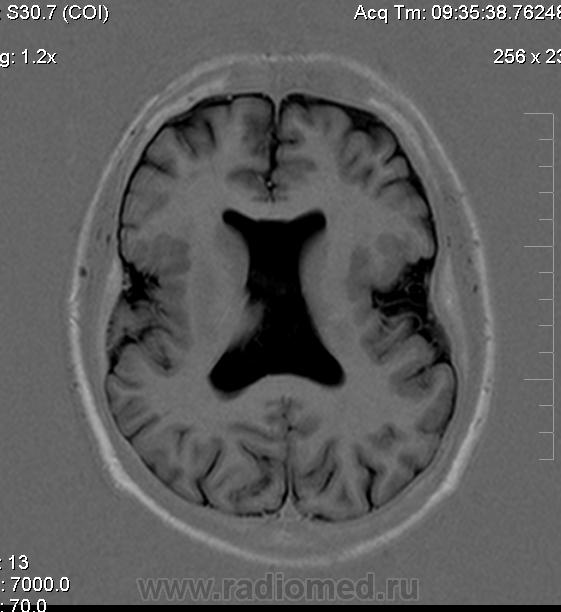

Мужчина 32 лет. Из анамнеза: перинатальное повреждение ЦНС, ДЦП, дизартрия, правосторонний верхний монопарез. С 16 лет приступы эпилепсии.

Аплазия прозрачной перегородки. Шизэнцефалия с открытыми краями в лобно-теменной области слева. Шизэнцефалия с закрытыми краями в лобной области справа? Утолщение коры по контуру расщелин и в области глазничной извилины правой лобной доли. Микрогирия? Гиперостоз костей свода черепа. Уважаемые коллеги, возможно я ошибаюсь, или есть еще аномалия?

На мой взгляд, полимикрогирия двусторонняя (конвекситальные отделы дорзальных отделов лобных долей и частично теменных, а также в базальном отделе полюса правой лобной доли) + закрытая шизенцефалия левой лобно-теменной области. Аплазия прозрачной перегородки (как признаки лобарной голопрозенцефалии).